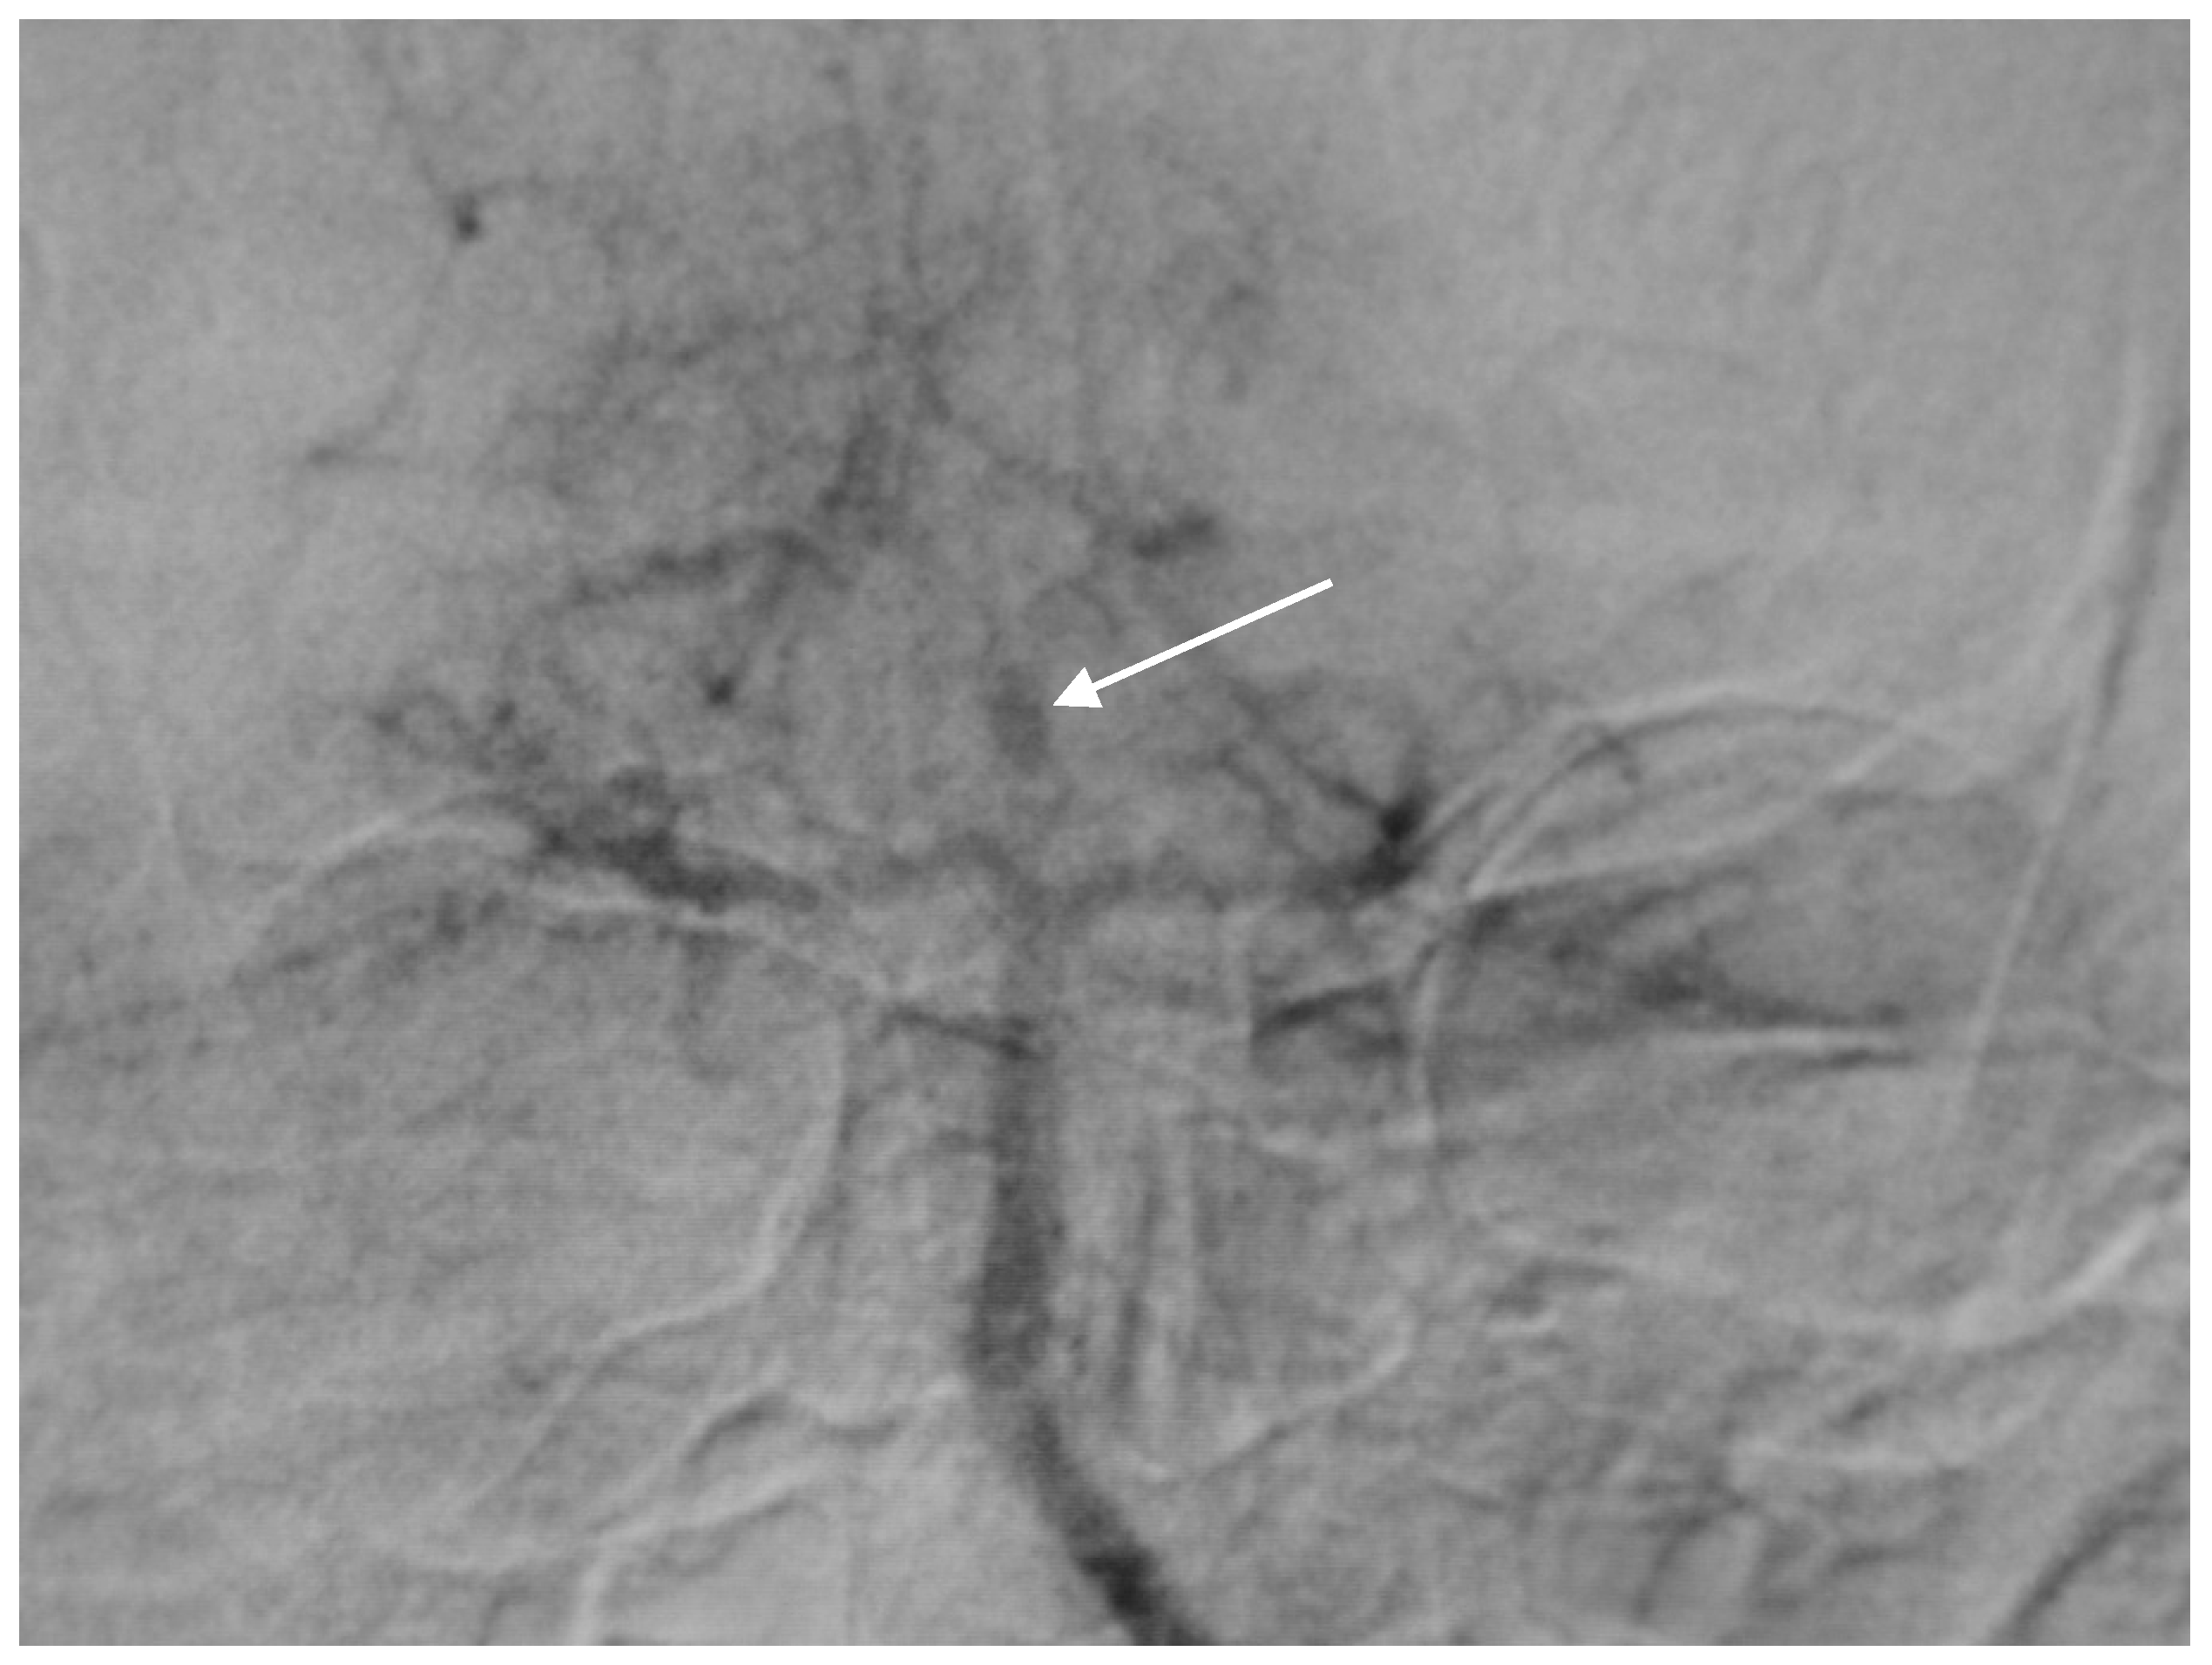

A 50-year-old man presented with a headache. Magnetic resonance imaging (MR) and angiography showed cerebellar AVM and two aneurysms on the right side of the PICA (Figure 6 and Figure 7). The patient underwent an operation, and AVM was successfully resected with both aneurysms clipped. The control angiogram showed good result of the treatment (Figure 8), the postoperative course was without complication, and the patient was discharged.

Figure 6. Anteroposterior (AP) angiogram showing cerebellar AVM (short arrow) and two PICA aneurysms (long arrow).